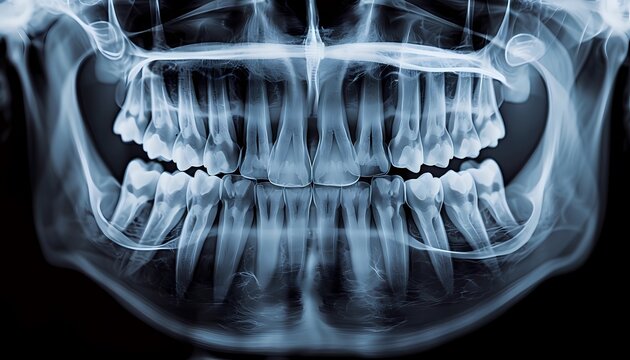

Dental X-Ray

A dental X-ray is an imaging technique used by dentists to see inside your mouth and jaw, revealing issues like cavities, bone loss, infections, and impacted teeth that aren’t visible during a visual exam. The process uses a low-dose of radiation to create images of your teeth, gums, and bones, helping dentists diagnose problems, plan treatment, and monitor oral health.